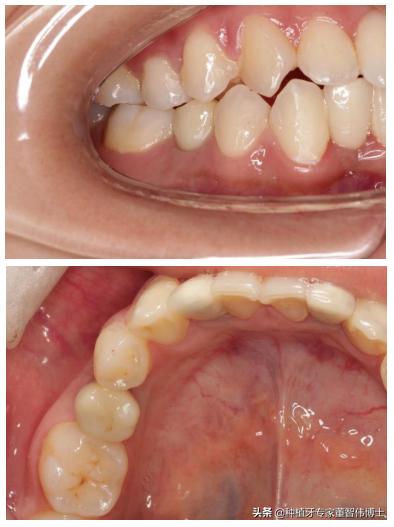

术后修复效果,可见修复体位置及形态良好

术后X线片显示种植体位置好,修复体形态恢复良好